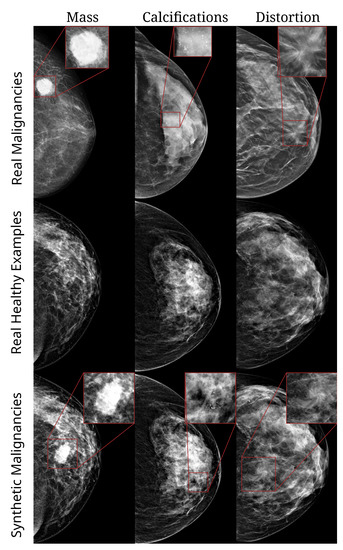

Three types of malignant lesions were inserted, namely, masses, calcifications, and architectural distortions, examples of which are shown in Figure 1. The methodology underlying the generation of these synthetic lesions has been described in detail in [34] and has previously been employed for lesion segmentation [33]. We will give a brief description here.

Figure 1.

Examples of images from HMI dataset. Top row: real malignant examples of a mass, cluster of calcifications, and architectural distortion, respectively. Second row: healthy/normal breasts. Third row: healthy breasts with synthetic lesions (mass, calcifications, and distortion, respectively).